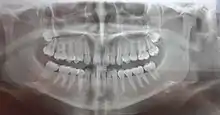

Galería de imágenes